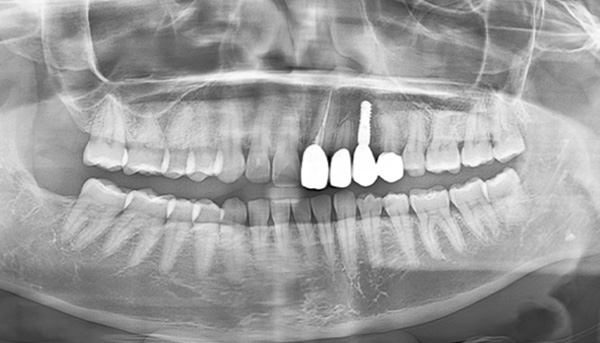

【50代男性】前歯のインプラント症例

「事故で下の歯を欠損したのを治したい」

治療前

治療後

CT画像

| 主訴 | 事故で怪我したため、欠損した箇所を治したい |

|---|---|

| 治療期間 | 約9ヶ月 |

| 治療費 | 合計1,600,000円(税別) 下の歯だけのインプラント:100万円(税別) |

| 治療内容 | 事故で骨内に入り込んだ歯を整復して、修復治療・欠損した箇所についてはインプラント治療を行いました。 ・GBRで骨造成を行い、インプラント2本を埋入し、ブリッジにて治療。 ・エクストリュージョン(歯根挺出術)。 |

| 治療のリスク | 前歯のインプラント治療では、審美性の問題や骨密度不足によるインプラントの不安定、神経損傷や感染のリスクがあり、術後の腫れや痛みも発生する可能性があります。 |